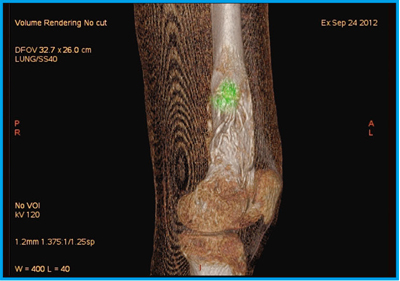

●症例5:骨肉腫化学療法後のThallium imaging

症例5は,骨肉腫化学療法の治療効果判定のためにタリウム(201Tl)シンチグラフィを撮像し,左大腿遠位にごく粗い集積が見られたが,reduction ratioは78%と著明に減少していた。集積残存の局在は不明なため,SPECT/CTを施行した。201Tl・SPECTで残存集積を緑色で表示し,CTの3D VR画像とフュージョンしたところ,viable regionが辺縁部に限局していると考えられた(図9)。

CT 3D VR画像で生検時の皮膚の傷口が認められ,フュージョン画像を皮膚面から透過して見ると傷口の高さとほぼ同じ位置に病変の残存があることが確認できた。CTの併用により,局在を明らかにできるメリットは大きいと言える。

図9 症例5:骨肉腫化学療法後のCT 3D VR画像とSPECTのフュージョン画像